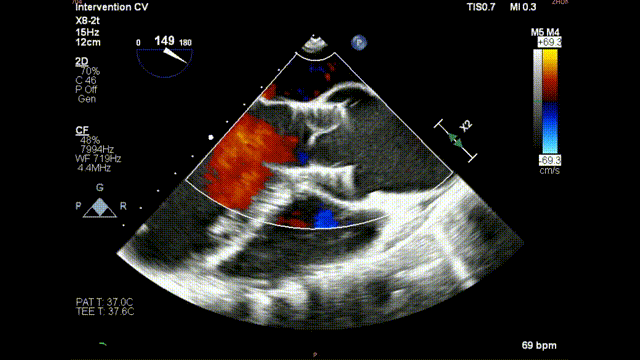

术后食道超声示:

术后食道超声-短轴

术后食道超声-长轴

术后食道超声-短轴color

术后食道超声-长轴color